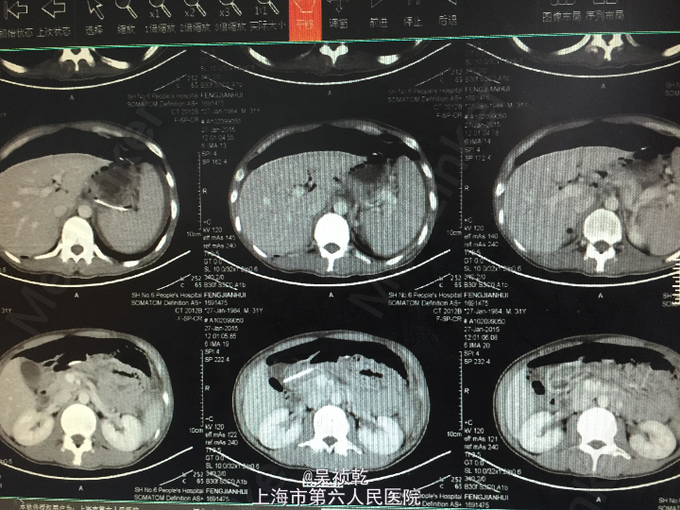

查体:神清,气平。BP 100/61mmHg,皮肤粘膜无黄染,无肝掌,无蜘蛛痣,全身浅表淋巴结无肿大。双肺呼吸音清,未及湿啰音,心率72次/分,律齐,无杂音。腹部平坦,全腹无压痛、反跳痛及包块,肝脾肋下未及,移动性浊音(-),肠鸣音不亢,双下肢无水肿。 辅查:2015-1-19 血沉检验报告:血沉 76 mm/h ↑。门诊化验检验报告:凝血酶原时间 12.3 秒 ,国际标准化比率 1.12 ,部分凝血活酶时间 42.0 秒 ↑,纤维蛋白原 3.560 g/L ,凝血酶时间 19.0 秒 。门诊化验检验报告:白细胞 3.3 *10^9/L ↓,红细胞 4.86 X10^12/L ,血红蛋白 82 g/L ↓,血小板 435 X10^9/L ↑,中性细胞百分比 61.0 % 。放免DPC(同位素)检验报告:甲胎蛋白(AFP) 1.79 ng/mL ,癌胚抗原(CEA) 1.38 ng/mL ,前列腺特异抗原 0.621 ng/mL ,游离前列腺抗原 0.111 ng/mL ,fPSA/PSA 0.179 ,鳞状上皮细胞癌抗原 0.50 ug/L ,糖类抗原(CA125) 18.53 U/mL ,糖类抗原(CA153) 18.47 U/mL ,糖类抗原(CA199) 3.43 U/mL ,神经元特异烯醇化酶 16.16 ug/L ,糖类抗原(CA242) 0.96 IU/ml ,糖类抗原(CA50) 3.73 IU/ML 。免疫检验报告:血清高敏C反应蛋白 44.60 mg/L ↑。 免疫检验报告:乙肝表面抗原 (-)0.02 IU/ml ,乙肝表面抗体 (+)538.3 mIU/ml P,乙肝e抗原 (-)0.263 S/CO ,乙肝e抗体 (+)0.07 S/CO ,乙肝核心抗体 (+)10.42 S/CO 。 免疫检验报告:抗丙肝病毒抗体 0.04 。2015-1-20 生化检验报告:血清铁 2.10 umol/l ↓,总铁结合力 47.30 umol/l ,铁饱和度 4.4 % ↓。 免疫检验报告:抗U1-RNP/Sm 阴性 ,抗SM 阴性 ,抗SS-A 阴性 ,抗Ro-52 阴性 ,抗SS-B 阴性 ,抗Scl-70 阴性 ,抗PM-Scl 阴性 ,抗Jo-1 阴性 ,抗着丝点 阴性 ,抗PCNA 阴性 ,抗dsDNA 阴性 ,抗核小体 阴性 ,抗组蛋白 阴性 ,抗核糖体P蛋白 阴性 ,抗线粒体抗体-M2 阴性 。免疫检验报告:抗单链DNA抗体(定量) <2.00 IU/ml ,抗双链DNA抗体(定量) <10.00 IU/ML 。2015-1-21 放免DPC(同位素)检验报告:铁蛋白(FERRITIN) 7.50 ng/mL ,叶酸 9.14 ug/L ,维B12 327.00 ng/L 。2015-2-6 血常规检验报告:白细胞 3.8 X10^9/L ,红细胞 4.21 X10^12/L ↓,血红蛋白 81 g/L ↓,血小板 200 X10^9/L ,中性细胞百分比 62.2 % 2015-1-19 CT报告检查报告:1.结肠肠内容物较多,请结合临床。2.前列腺钙化灶。 2015-1-20 心电图报告检查报告:正常心电图。 普放报告检查报告:心肺X线未见明显活动性病变。 2015-1-22 肠镜报告检查报告:结肠节段溃疡病变性质待定。 2015-1-27 普放报告检查报告:右腹部小肠轻度扩张积气,立位见小气液平面,两侧膈下见游离气体影。余腹部平片未见明显异常密度病灶。2.两侧膈下游离气体影,考虑上消化道穿孔可能大。1.小肠轻度扩张伴液平,肠梗阻待排,请结合临床。 CT报告检查报告:1.腹腔大量游离气体伴积液,建议结合下腹部CT报告。2.脾脏稍肿大,阑尾少许粪石沉积。 术后病理检查报告:乙状结肠 (乙状结肠)粘膜组织慢性炎,表面腺体呈腺瘤样增生,请结合临床。

患者入院后予以完善相关检查(血尿便常规、肝肾功能电解质、心电图、胸片、肠镜等);1.22 患者今日下午行肠镜检查术,术顺安返病房。患者于2015.01.27晨5:00诉腹痛,中上腹为主,放射至下腹部,无发热,无恶心、呕吐,有排气,无排便,腹痛与排气无相关,予以腹部平片检查:1-27腹部平片:膈下游离气体,穿孔可能。请普外科会诊,诊断意见:消化道穿孔可能,转普外科急诊剖腹探查手术,术中见腹腔内大量脓液,探查发现乙状结肠距腹膜折返约15cm处狭窄伴穿孔,将乙状结肠穿孔处拖出切口,造瘘一期开放。术后予补液抗炎等对症处理,目前患者恢复可,予出院。出院诊断:1.急性腹膜炎,2.消化道穿孔,3.溃疡性结肠炎,4.中度贫血